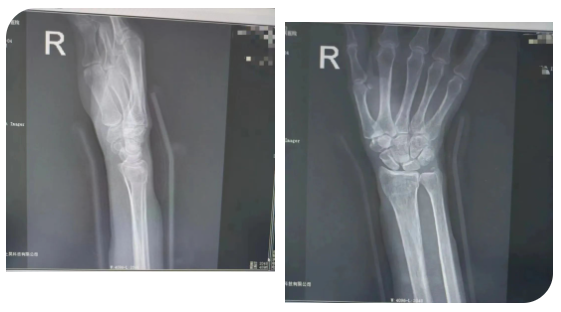

马女士(化名)于2年前因外伤导致“右侧桡骨远端骨折”,找当地赤脚医生行“包草药”治疗。后逐渐发现右侧腕部尺侧凸起畸形,腕关节尺偏活动受限,患者未予重视。

近3月来,患者抱孙子后出现右尺侧腕关节疼痛,前臂旋前时疼痛加重,握力减弱明显,感受到身体的异样后,便到医院创伤外科就诊。